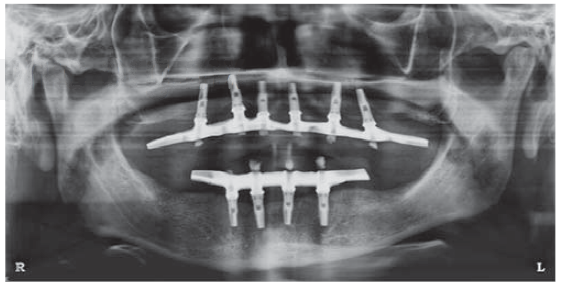

Después de seis meses se evaluó radiográficamente, observando el tejido óseo periimplantario conservado sin ningún signo que evidencia complicaciones. Seguidamente, se realizó la exposición quirúrgica y colocación de los tornillos de cicatrización, observándose la oseointegración de todos los implantes.

Prótesis implantosoportada

Dos semanas después se inició con la confección de las prótesis implantosoportadas de ambos maxilares. El diseño de ambas prótesis fueron de tipo híbrido (anclaje óseo completo).

Se realizó el seguimiento del caso durante un periodo de 18 meses, sin presentar complicaciones y con un resultado funcional y estético satisfactorio (Figura 12).